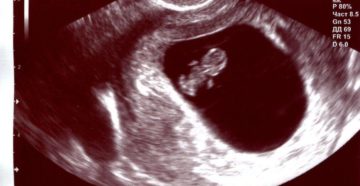

Основные задачи УЗИ на 8 неделе беременности Практически каждый определенный период во время беременности требует…

8 неделя беременности — В положении 1 8 неделя беременности: что происходит с малышом и…